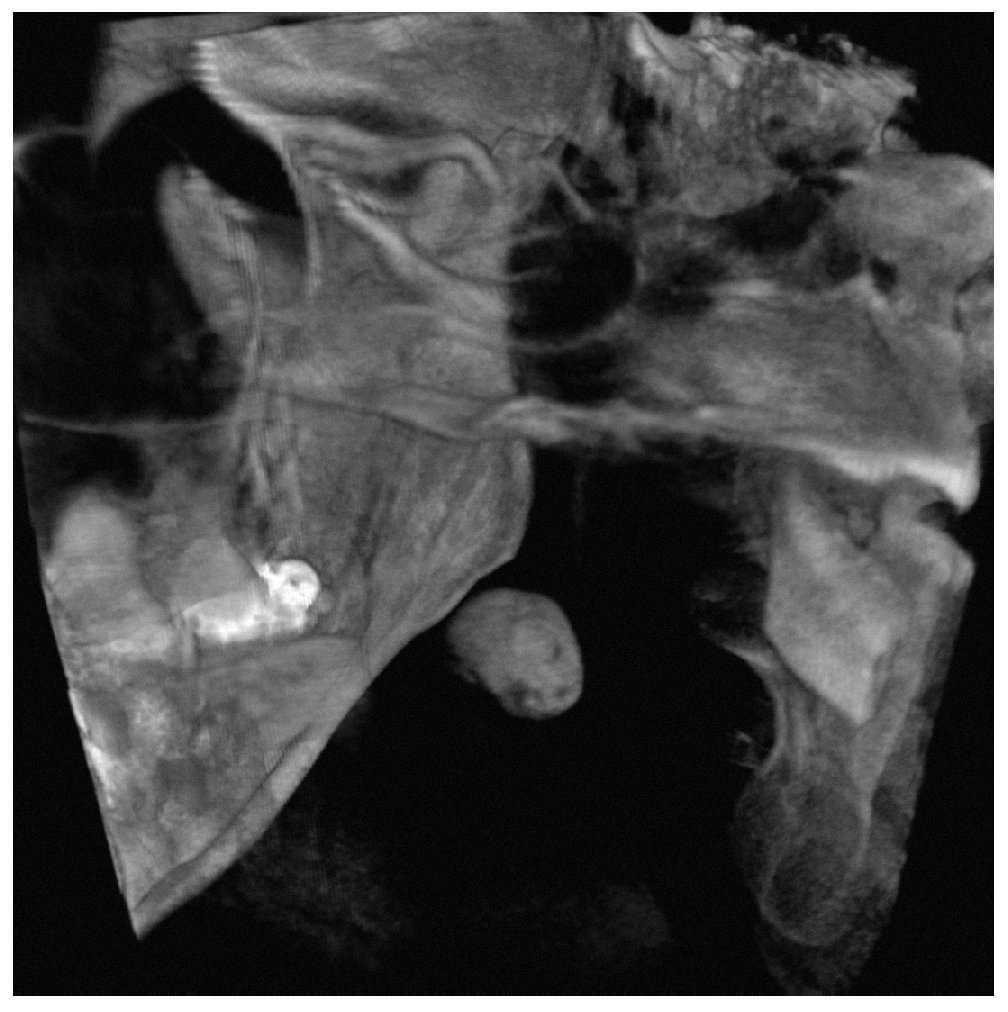

Caso 634, mujer, 42 años

Calcificación parafaríngea derecha: tonsilolito

La paciente acudió a la consulta para el estudio diagnóstico de una imagen radioopaca observada como hallazgo casual en una radiografía panorámica (fig. 1). En el interrogatorio, la paciente refirió no sentir ningún tipo de molestia.

Figura 1. Radiografía panorámica.

Se obtuvo una tomografía volumétrica digital dental para completar el estudio diagnóstico. En la tomografía destacó a 1,5 cm en medial de la rama mandibular derecha una masa redondo-ovalada, hiperdensa y bien delimitada con un tamaño de aproximadamente 12 x 10 mm localizada en los tejidos blandos parafaríngeos (figs. 2 a 4). De este modo se descartó con certeza la presencia de un sialolito.

Figura 4. Tomografía volumétrica digital dental: imagen desde anterior y craneal con representación volumétrica.